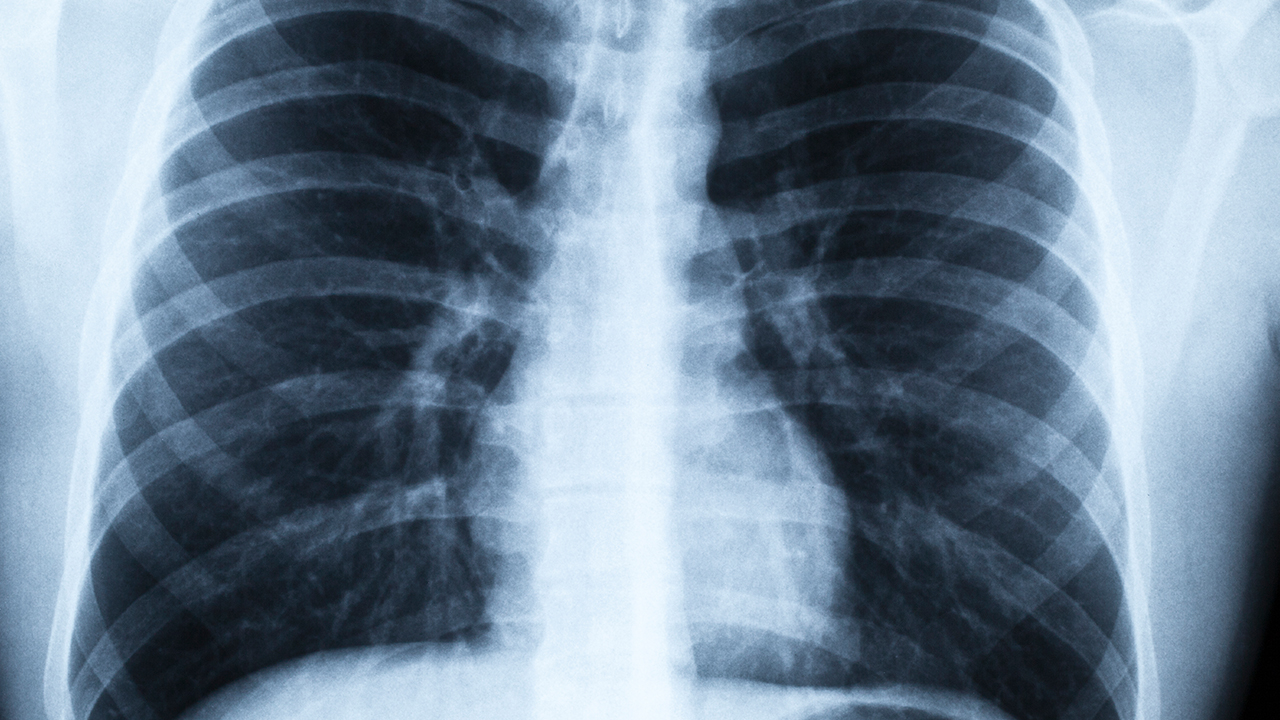

肺结核的自然病程较长,部分免疫系统较强的患者可能出现症状暂时缓解,但病灶中的结核杆菌仍可能存活并伺机复发。轻度肺结核患者可能出现低热、盗汗、乏力等非特异性症状,胸部影像学检查可显示局限性病灶。这类患者若未接受规范治疗,病灶可能缓慢进展为纤维化或钙化,但无法清除体内结核杆菌,存在远期复燃风险。

极少数免疫功能健全的感染者可能通过自身免疫力抑制结核杆菌繁殖,但这种情况多见于原发性肺结核且病灶范围极小者。即使影像学显示病灶吸收,仍需通过痰培养、分子生物学检测等确认病原体清除,而3个月时间通常不足以完成这一过程。临床上将这类情况称为生物学而非真正自愈,仍存在细菌复燃可能。